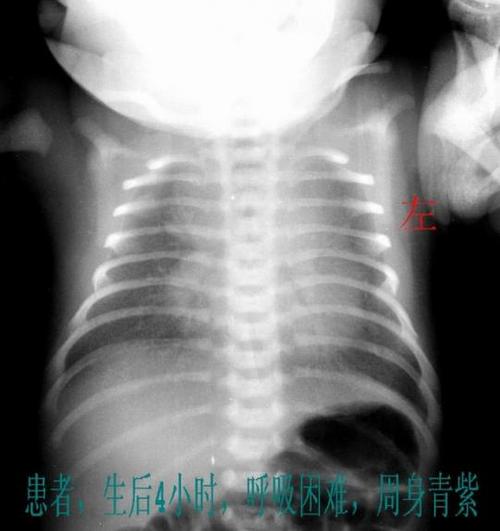

新生儿,尤其是早产儿或患有新生儿肺炎、呼吸窘迫综合征的宝宝,病情变化极快,且无法用语言表达,肺部拍片(胸片)是目前评估新生儿肺部状况最直接、最快速、最有效的“眼睛”。

- 精准诊断: 快速识别是肺炎、肺不张、湿肺,还是更为复杂的先天性肺疾病,没有准确的诊断,后续治疗就是“盲人摸象”。

- 指导治疗: 根据胸片显示的病变范围和严重程度,医生可以精准判断是否需要使用抗生素、呼吸机支持,以及调整呼吸机的参数,这是决定宝宝生死和预后的关键一步。

- 评估疗效: 在治疗过程中,定期复查胸片可以直观地看到病情是好转还是恶化,为调整治疗方案提供客观依据。

- 避免误诊和过度治疗: 准确的诊断可以避免将其他疾病误诊为肺炎而滥用抗生素,也可以避免漏诊真正的重症而延误治疗。

一句话总结:在新生儿危重呼吸系统疾病的诊断和治疗中,肺部拍片所带来的“信息价值”和“临床指导价值”,远远大于其那微乎其微的辐射风险。